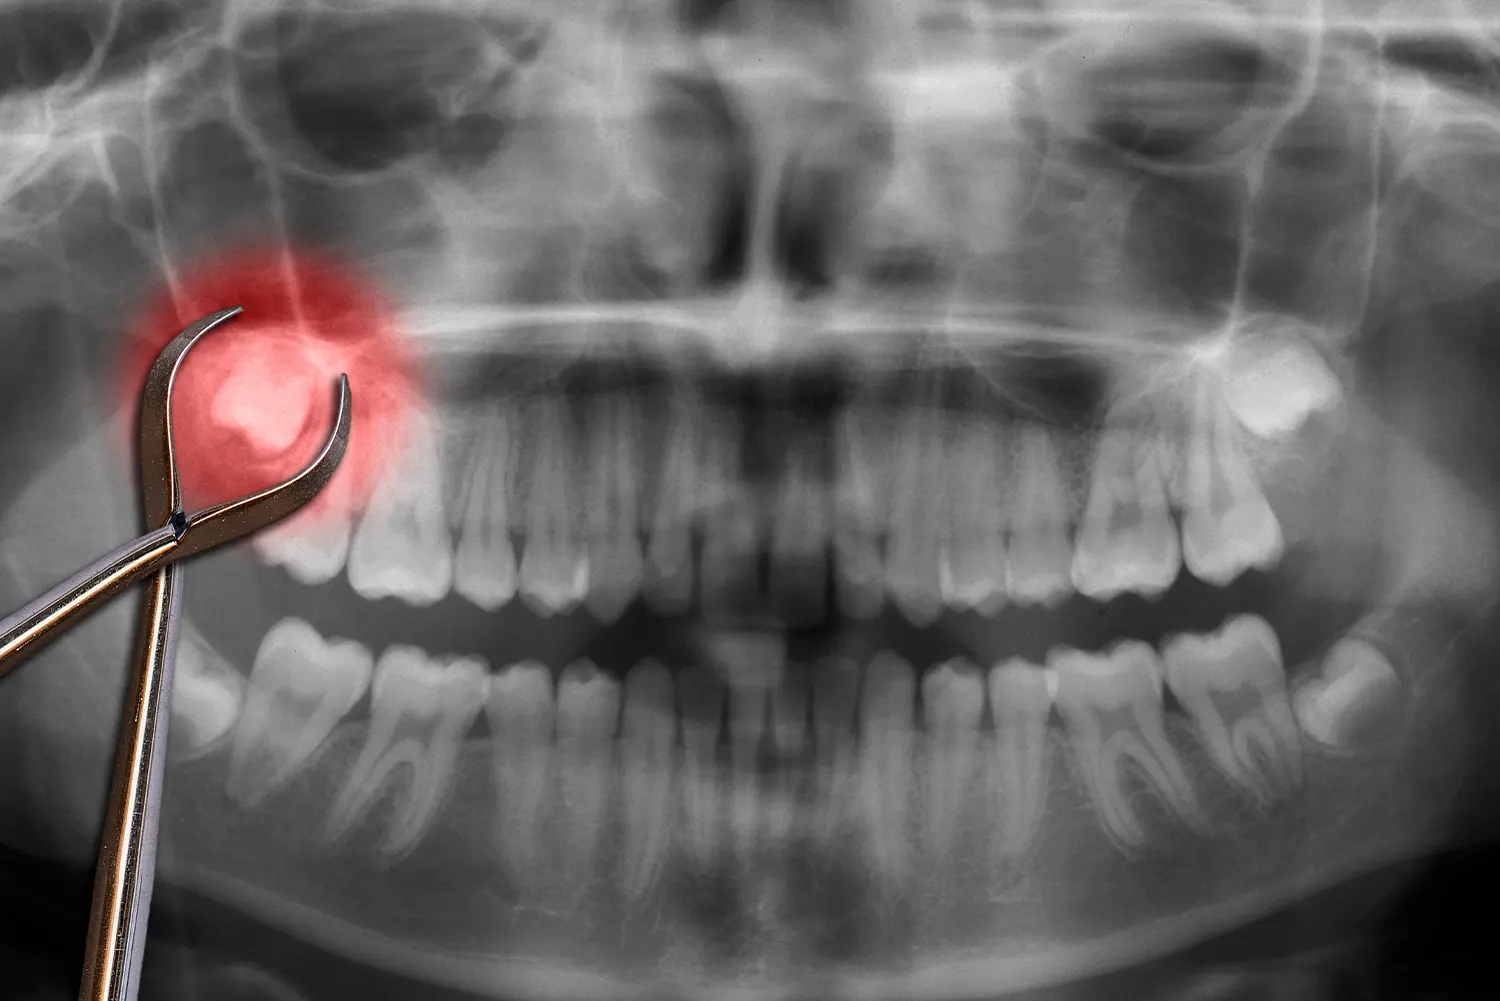

Wisdom teeth removal is a common oral surgery that can prevent more serious dental issues when performed at the right time. At Trillium Oral Surgery and Implantology, our board-certified surgeons specialize in the safe and compassionate removal of third molars, commonly known as wisdom teeth.

These teeth often become impacted or misaligned, leading to pain, infection, or damage to neighboring teeth. By offering evidence-based care and a calm, reassuring environment, our team ensures each patient feels at ease before, during, and after the procedure. Whether you’re just starting to feel symptoms or are looking for a second opinion about your wisdom teeth, we’re here to help with expert care right in your community.

Prevent Painful Impactions

When wisdom teeth become trapped under the gums or grow at awkward angles, they can cause ongoing pain or infections. Removal eliminates this discomfort and preserves dental health

Initial Consultation and Imaging

During your first visit to our Chelsea clinic, a Trillium oral surgeon will carefully evaluate your mouth using digital imaging to assess the position and development of your wisdom teeth. This step allows us to create a tailored plan that addresses your unique oral health landscape and minimizes risks. Each consultation is patient-focused, with plenty of time for questions and one-on-one discussion to ensure you’re fully informed and at ease.